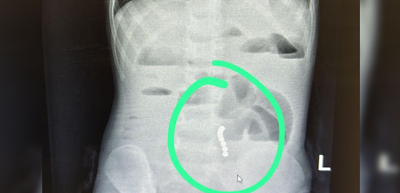

הילד התלונן על כאבי בטן והקיא הרבה, לאחר שהגיע לבית החולים יחד עם הוריו, התברר לאחר סדרת בדיקות מקיפות, כי הילד בלע שמונה מגנטים; "ההורים נקראים להרחיק מגנטים וחלקים קטנים מהישג ידם של ילדים" (חדשות בריאות)

עקב השהות הממושכת של המגנטים במערכת העיכול, והיצמדות חלקים מצינור העיכול האחד לשני ע"י המגנטים, חדרו כמה מגנטים את דופן הקיבה, ולא ניתן היה לשלוף אותם מבלי לסכן את חיי הפעוט. בעקבות זאת הוכנס התינוק לניתוח חירום, לאחר הניתוח הוא הועבר במצב טוב למחלקה (חדשות בריאות)